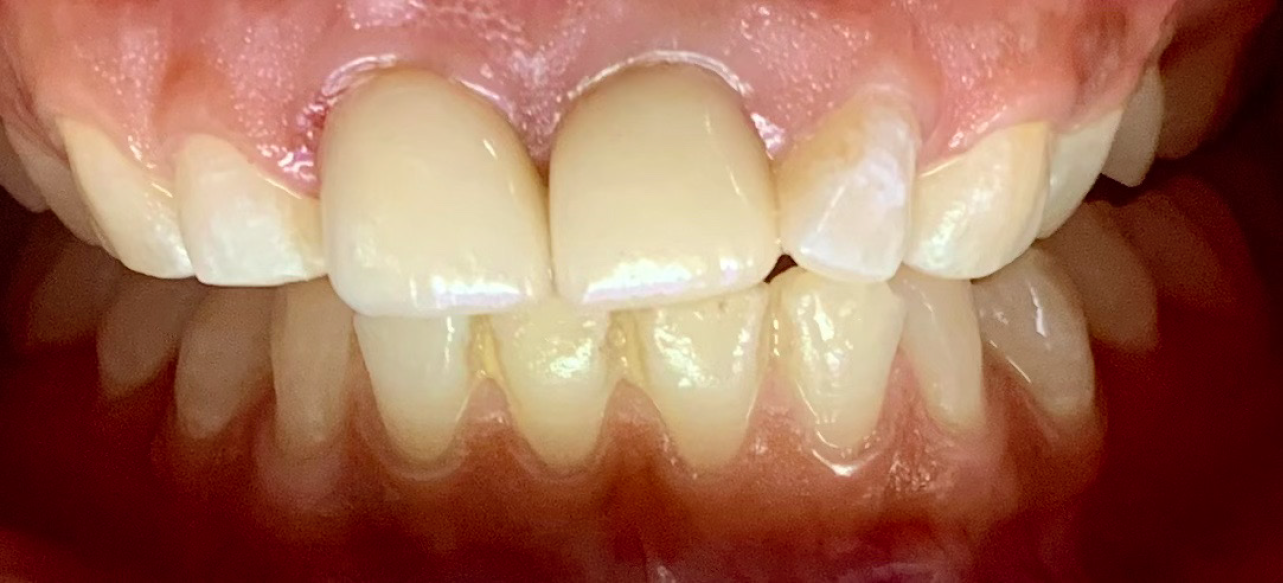

Figure 11 Shows the clinical image of Emax crowns wrt 11 and 21.